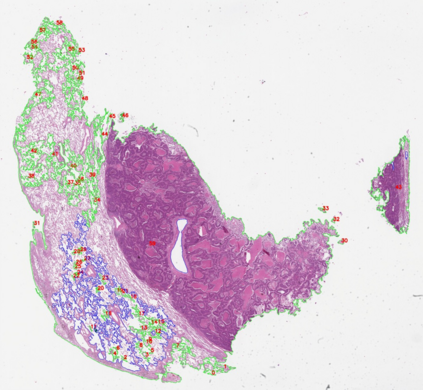

Multiple instance learning (MIL) is a powerful approach to classify whole slide images (WSIs) for diagnostic pathology. A fundamental challenge of MIL on WSI classification is to discover the \textit{critical instances} that trigger the bag label. However, previous methods are primarily designed under the independent and identical distribution hypothesis (\textit{i.i.d}), ignoring either the correlations between instances or heterogeneity of tumours. In this paper, we propose a novel multiplex-detection-based multiple instance learning (MDMIL) to tackle the issues above. Specifically, MDMIL is constructed by the internal query generation module (IQGM) and the multiplex detection module (MDM) and assisted by the memory-based contrastive loss during training. Firstly, IQGM gives the probability of instances and generates the internal query (IQ) for the subsequent MDM by aggregating highly reliable features after the distribution analysis. Secondly, the multiplex-detection cross-attention (MDCA) and multi-head self-attention (MHSA) in MDM cooperate to generate the final representations for the WSI. In this process, the IQ and trainable variational query (VQ) successfully build up the connections between instances and significantly improve the model's robustness toward heterogeneous tumours. At last, to further enforce constraints in the feature space and stabilize the training process, we adopt a memory-based contrastive loss, which is practicable for WSI classification even with a single sample as input in each iteration. We conduct experiments on three computational pathology datasets, e.g., CAMELYON16, TCGA-NSCLC, and TCGA-RCC datasets. The superior accuracy and AUC demonstrate the superiority of our proposed MDMIL over other state-of-the-art methods.